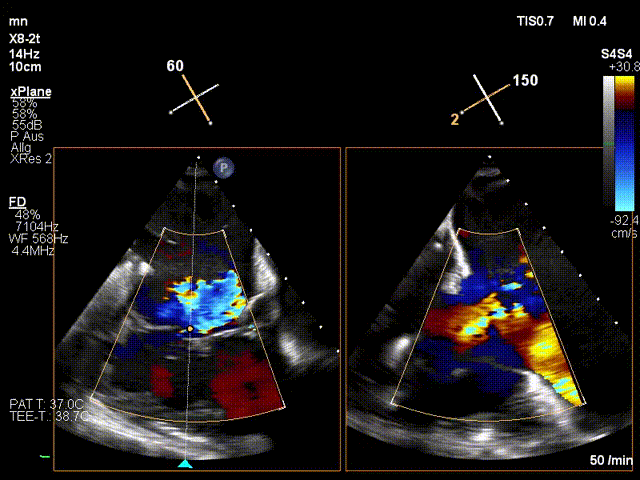

手術在全麻狀態下進行。在加拿大圣保羅醫院的Anson Cheung教授的指導參與下,術者采用經右側頸靜脈入路的方式將輸送器送入患者心臟內,在TEE及DSA引導下調整輸送器頭端角度,使得輸送器與三尖瓣瓣環平面垂直。在輸送器進入右心室后釋放室間隔錨定裝置,而后釋放瓣葉夾持件(2個耳片結構)成垂直狀態。在TEE及DSA確定夾持件固定至三尖瓣葉根部且位于右室側后釋放人工瓣心房側盤片。隨后調整瓣膜同軸性以及室間隔錨定件位置(貼合室間隔),前推藏針管并固定,進而釋放室間隔錨定裝置,并再次確認瓣膜位置、穩定性及同軸性,合攏輸送鞘后撤出輸送器,完成LuX-Valve Plus人工三尖瓣瓣膜的植入。

LuX-Valve Plus經血管三尖瓣置換系統本次“出海”圓滿完成,術后Jörg Hausleiter教授對LuX-Valve Plus經血管三尖瓣置換系統的器械性能和治療效果大為稱贊,認為LuX-Valve Plus的手術體驗非常好。術后即刻超聲顯示三尖瓣反流消失,血流動力學改善顯著,患者恢復快。Anson Cheung教授也肯定了LuX-Valve Plus術中操作的便捷性,認為LuX-Valve Plus容錯率高,對術中影像的依賴較小,后期希望可以更多的應用LuX-Valve Plus三尖瓣置換系統于臨床實踐,讓更多的三尖瓣重度反流患者盡早獲益,改善預后。